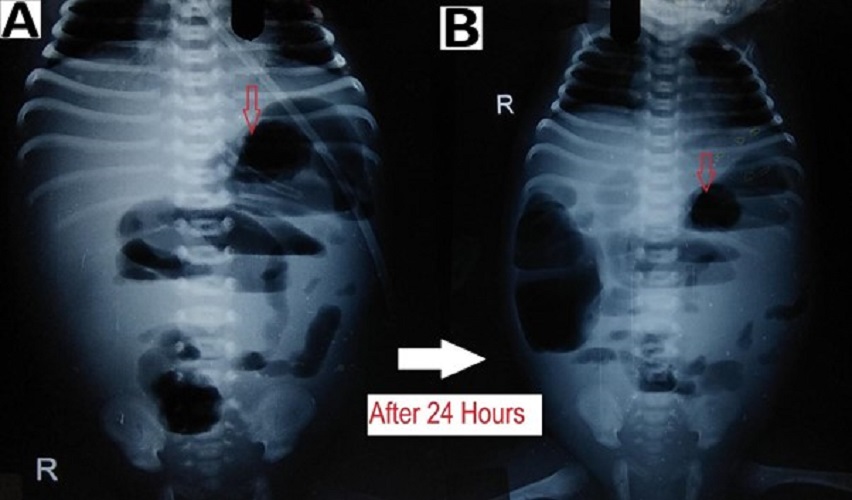

Figure 3

Preoperative radiographs showing: (A) dilated bowel loops (red arrow) at the left upper abdomen and (B) fixed dilated bowel loops (red arrow) at an interval of 24 hours.